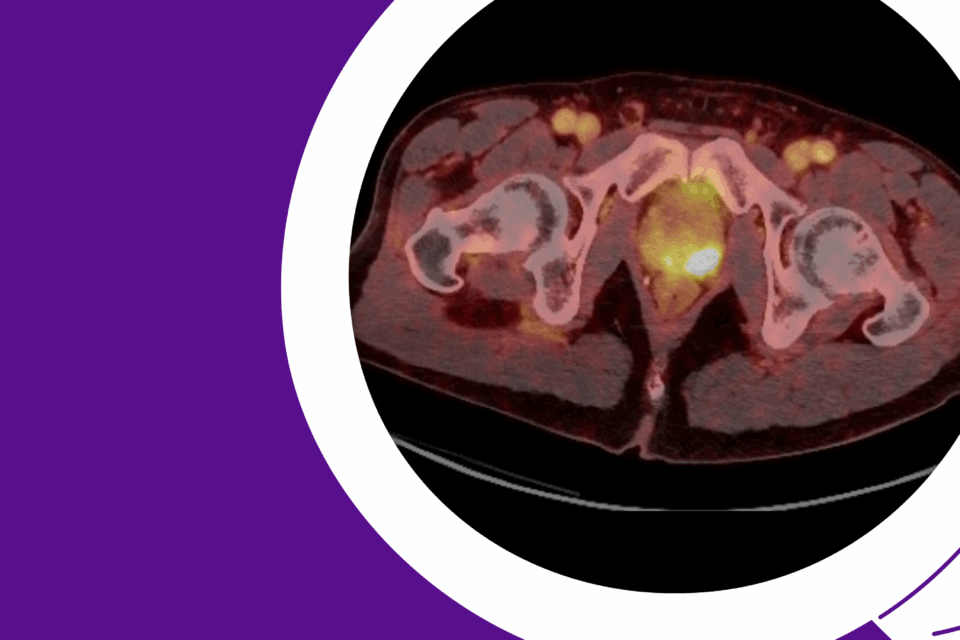

Robotic Management of Giant Hydronephrosis & Contralateral UPJ Obstruction

Dr. Brian W. Chao details his approach to robotic nephrectomy and pyeloplasty for incidentally discovered giant hydronephrosis and contralateral UPJ obstruction.